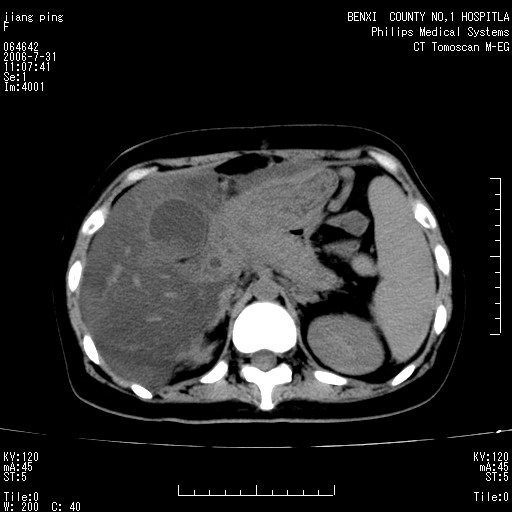

以下是引用晓杰在2006-8-1 9:01:00的发言:[br]支持营养不良导致脂肪肝。[br]胰头增大界限不清,考虑为胰腺炎破坏十二指肠粘膜、肠壁增厚、肠腔狭窄,并与胰头粘连所致

以下是引用jiajie在2006-7-31 20:34:00的发言:[br]支持营养不良导致脂肪肝。[br]胰头增大界限不清,考虑为胰腺炎破坏十二指肠粘膜、肠壁增厚、肠腔狭窄,并与胰头粘连所致。